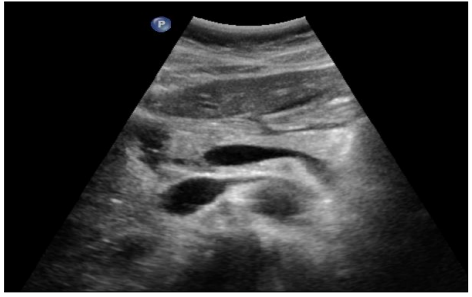

Foie : maladie chronique

DANSE E. - UCL

MASTER 1